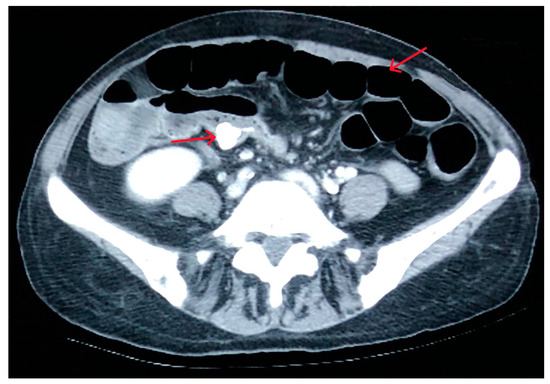

2. Case Presentation